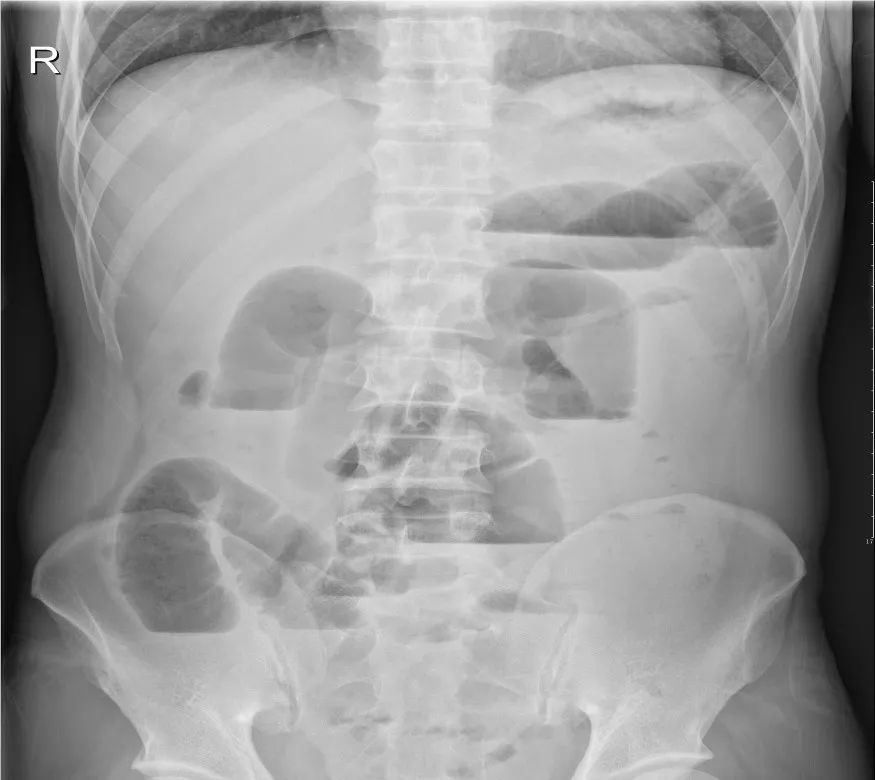

6)肠梗阻:任何原因引起的肠内容物通过障碍统称肠梗阻。临床表现为腹痛腹胀、恶心呕吐、停止排气排便等症状。X线立位腹平片是诊断本病的重要检查手段。CT可用于寻找梗阻原因及鉴别诊断。

小肠不全梗阻:腹部立位平片可见小肠扩张,积气、积液,伴多发气液平面,呈阶梯状排列;CT平扫,小肠扩张,积气、积液。